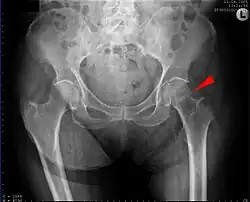

Intertrochanteric hip fracture in a 17-year-old male

Hip fracture classification.[17]

X-rays of the affected hip usually make the diagnosis obvious; AP (anteroposterior) and lateral views should be obtained.

Extracapsular Trochanteric Intertrochanteric (between the greater and lesser trochanter[18]) AO 31-A1 – 31-A2 Evans' classification (1949), Ramadier's classification (1956), Boyd and Griffin's classification (1949), Decoulx & Lavarde's classification (1969), Ender's classification (1970), Tronzo's classification (1973), Evans-Jensen classification (1975), Deburge's classification (1976), Briot's classification (1980)

Pertrochanteric (through the trochanters[18][19]) AO 31-A3

Trochanteric fractures are subdivided into either intertrochanteric (between the greater and lesser trochanter[18]) or pertrochanteric (through the trochanters[18][19]) by the Müller AO Classification of fractures.[20] Practically, the difference between these types is minor. The terms are often used synonymously.[21][22] An isolated trochanteric fracture involves one of the trochanters without going through the anatomical axis of the femur, and may occur in young individuals due to forceful muscle contraction.[23] Yet, an isolated trochanteric fracture may not be regarded as a true hip fracture because it is not cross-sectional.